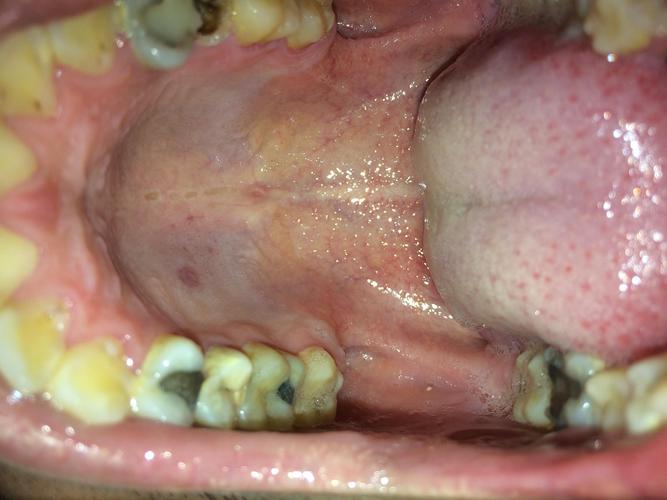

口腔上颚无痛硬块是何问题?

无痛的硬块,良性的可能性比较大,常见于以下几种情况:

粘液腺囊肿

这是口腔内非常常见的一种良性囊肿。

- 特点:通常是由于小唾液腺的导管被堵塞,分泌的唾液无法排出,形成一个充满透明或半透明粘液的囊袋,它可能看起来像一个小水泡或半透明的硬块,质地柔软或稍韧,一般没有痛感,但有时会因咬伤等原因突然变大。

- 位置:可以发生在口腔的任何部位,包括上颚、嘴唇内侧、脸颊内侧等。

口腔上颚的无痛硬块,绝大多数情况下是良性的粘液腺囊肿、腺样体增生或对刺激的正常反应。“无痛”并不等于“无害”,因为它也可能是某些严重疾病(如恶性肿瘤)的早期信号。